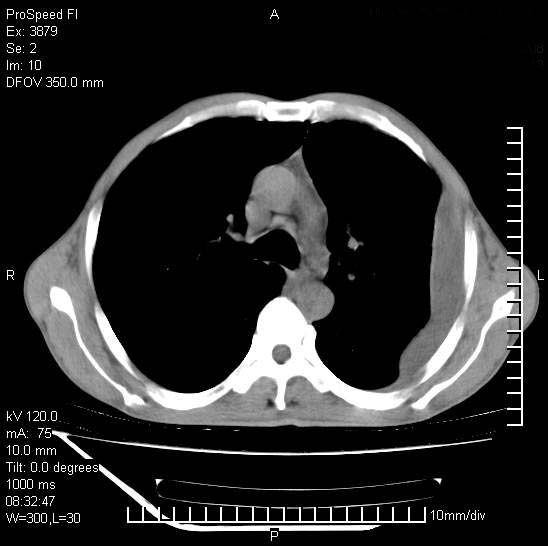

以下是引用37度在2008-6-6 11:20:00的发言:[br]1.包裹性积液,多考虑结核性;[br]2.穿刺术后改变。

以下是引用312nanyang在2008-6-6 15:12:00的发言:[br]基本支持楼主意见[br]疑问?左下肺支气管旁的软组织(16层)密度怎么解释?淋巴结还是斜裂胸膜增厚所致?能否增强进一步检查